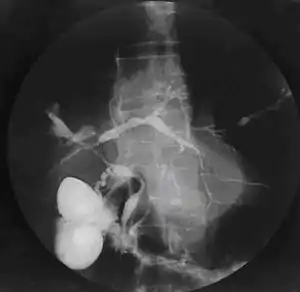

| Cholangiogram of primary sclerosing cholangitis. | |

Historically, a cholangiogram would be obtained via endoscopic retrograde cholangiopancreatography (ERCP), which typically reveals "beading" (alternating strictures and dilation) of the bile ducts inside and/or outside the liver. Currently, the preferred option for diagnostic cholangiography, given its non-invasive yet highly accurate nature, is magnetic resonance cholangiopancreatography (MRCP), a magnetic resonance imaging technique. MRCP has unique strengths, including high spatial resolution, and can even be used to visualize the biliary tract of small animal models of PSC.[19]